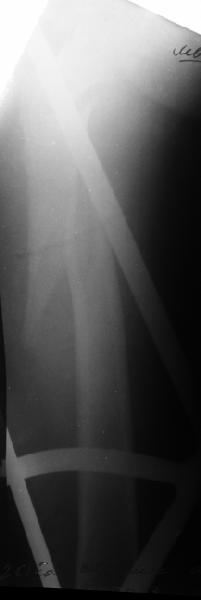

В диагноз пишем... Потом же как-то анализировать надо. Что-то никто не откликнулся на этот вопрос из англоязычных коллег. Все-таки - как такой перелом надо классифицировать? А если шейка бедра + диафиз? Завтра покажу такой случай.

Да, сейчас это и у нас самый напрашивающийся выбор. Сделали гвоздем ChM, картинки в приложении.